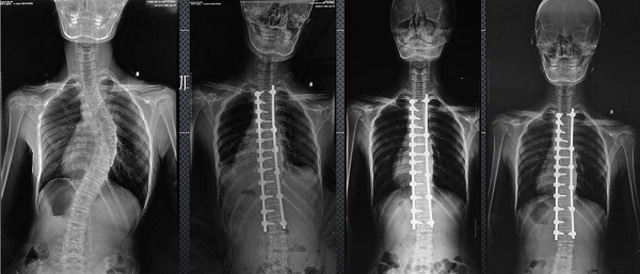

(7)全身拼接功能对有较大尺寸全脊柱拼接图接桂成金下股分成几次拍摄,再经过秋件开在骨科开展的全脊柱畸形矫治工作中,虽然CT. MRI也能获取全脊柱影像,接图像,以便于长度、角度、力线等测量和察脊柱在重力情况下但不能进行立位检查,无法观全景观察。全身拼接功能是高等级DR摄取患者立位全下的功能状态图像,因此采用动态医院特别看重的动态DR功能之一。注:图中Cobb脊柱正侧位图像是首选的检查方法角度的大小是反映侧弯严重程度的一个标准。